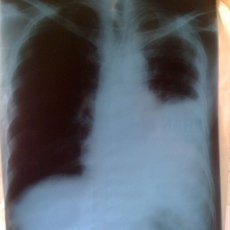

- Tràn máu màng phổi

- Chảy máu trong khoang màng phổi có thể gây khó thở.